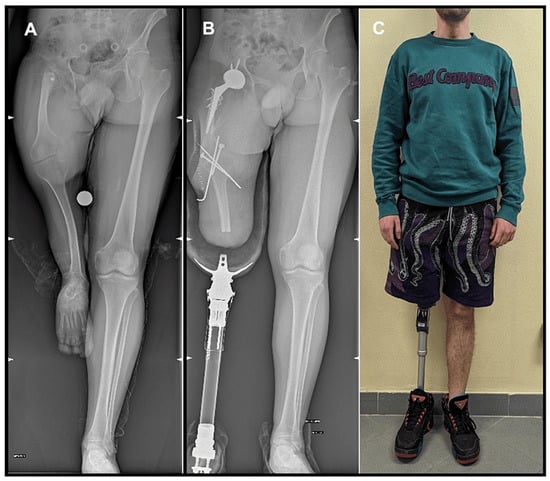

| Sanjeev Patnaik et al. [34] | Case report | 1 AKA | Trauma | 0.25 ys | Secondary OA | Uncemented components, anterolateral approach. | Day 2, ambulate with prosthesis on full weight bearing. | 12 months: ambulate with no aids. |

| Use of bone clamp in lesser trochanteric area. | No final ROM data. | |||||||